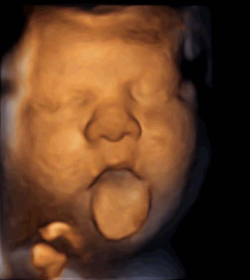

Los fetos sacan la lengua al máximo al “oír” la música

Sin embargo, cuando el estímulo musical se emite desde el interior de la vagina de la madre, los futuros bebés reaccionan abriendo la boca y sacando la lengua, con movimientos que la clínica de fertilidad catalana interpreta como “de vocalización, previos a la adquisición del lenguaje”.

Los expertos analizaron por ecografía la reacción de todos los fetos y observaron cómo el 87% de los bebés que recibieron música vía vaginal movieron la boca o la lengua y cerca del 50% reaccionó abriendo mucho la mandíbula y sacando la lengua al máximo. Sin embargo, en los bebés del resto de los grupos no se observaron ninguna de estas reacciones.